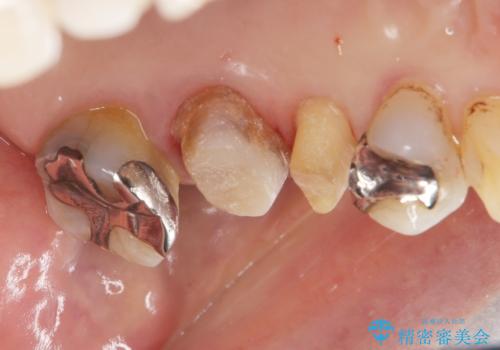

70代女性 段差のある被せ物のやり替え

- 左下の大臼歯(6番)の根の治療を行いました。

後方の歯が欠損していた為、インプラントをお勧めしましたが希望されませんでした。

その代わり、現在ある歯をしっかり治療することになり、左上下の治療を行っています。

左上56間が狭かったため、写真にはないですが、セパレーションを2回ほど行い、歯根間距離を広げてから処置を行っています。

歯と歯の間(特に歯根と歯根の間)が異常に狭いと歯型が正確にとれない上に歯間ブラシも入らないような歯の形態になり、セルフケアに支障がでてきます。